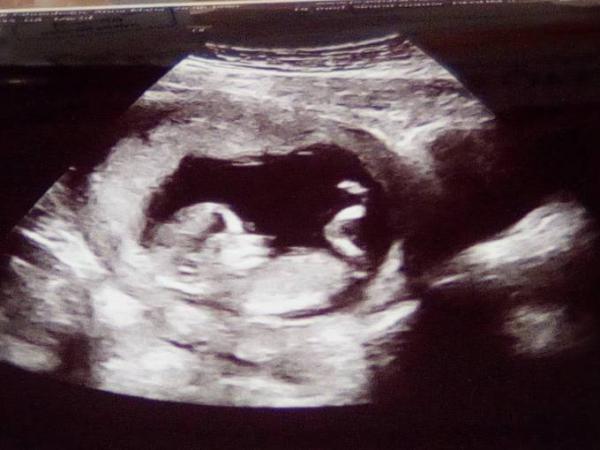

Achso, hier noch Bilder und es ist Knapp 6 cm groß und entspricht somit genau der Größe, die es in der SSW haben soll :)

Wir sind sooo Happy Happy Happy!! Heute war das Ersttrimesterscreening und sowohl mein Mann als auch ich waren sehr aufgeregt. Wir haben es allerdings nur zur reiner Vorsicht gemacht. Es war himmlisch! Trisomie 21 liegt bei einer Wahrscheinlichkeit von 1:16000 18 bei 1:39000 und 13 bei 1:27000! Auch die Ärztin meinte da braucht man eigentlich nicht drüber reden! Arme, beine, Schädel alles perfekt entwickelt. Der Herzschlag und die Versorgung genauso wie es sein soll

Es könnte nicht besser sein. Die Nackenfaltenmessung ist total unauffällig und das Nasenbein sehr gut darstellbar.